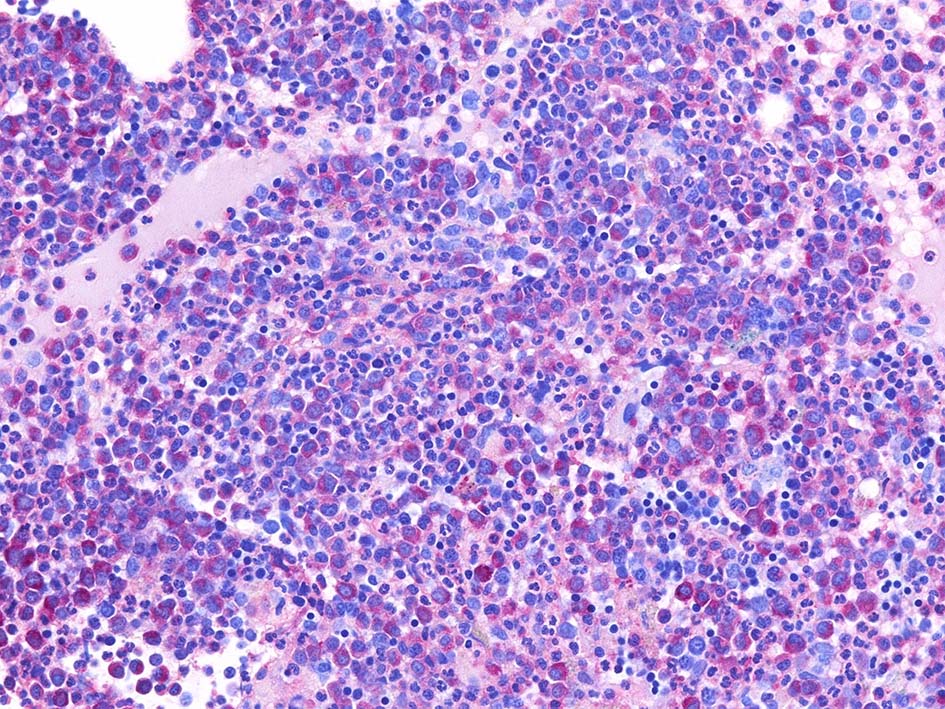

Naphtohl-ASD-CAE Fig.01

Fig.01: hypercellular marrow. ASDで赤染する細胞の増加=granulopoietic hyperplasiaがある.

Fig.02: 幼若な顆粒球が増加している. 赤芽球は散在しており血島は不明瞭である. 過形成髄なのにFig.02に成熟大型巨核球はみられない.

Fig.03: granulopoietic hyperplasia. 成熟顆粒球の増加もある.

Naphtohl-ASD-CAE